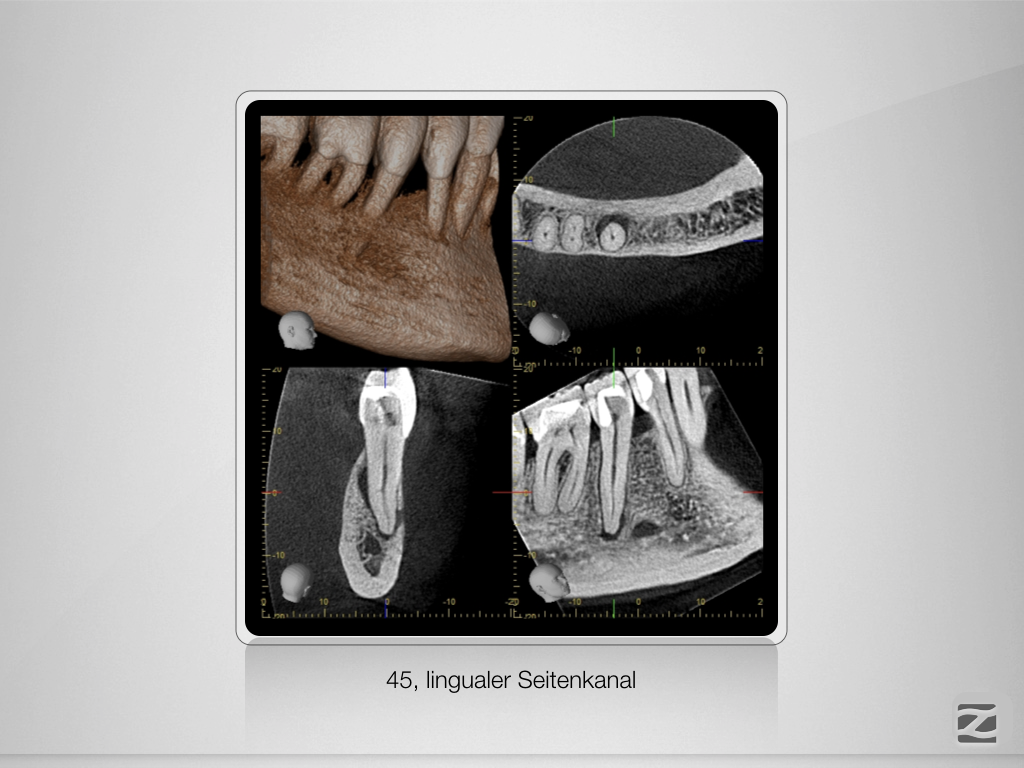

Fährtensuche